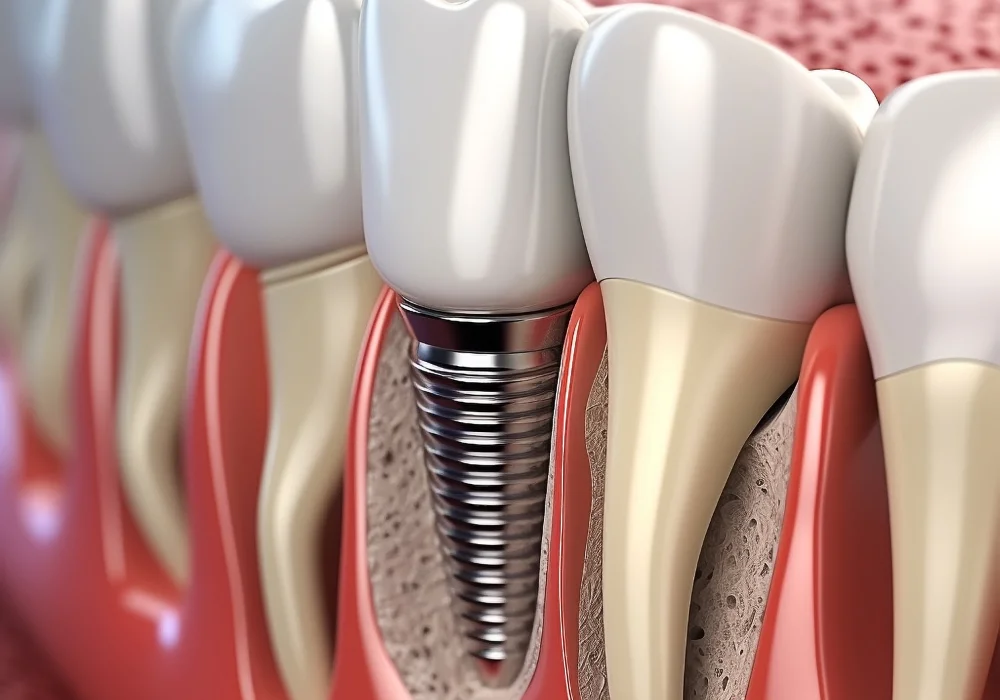

La rehabilitación oral combina diferentes tratamientos dentales para restaurar dientes dañados, reemplazar piezas perdidas y mejorar la mordida, devolviéndote la seguridad de sonreír y masticar sin problemas.

Con especialistas certificados y tecnología moderna, diseñamos un plan de rehabilitación oral a tu medida.